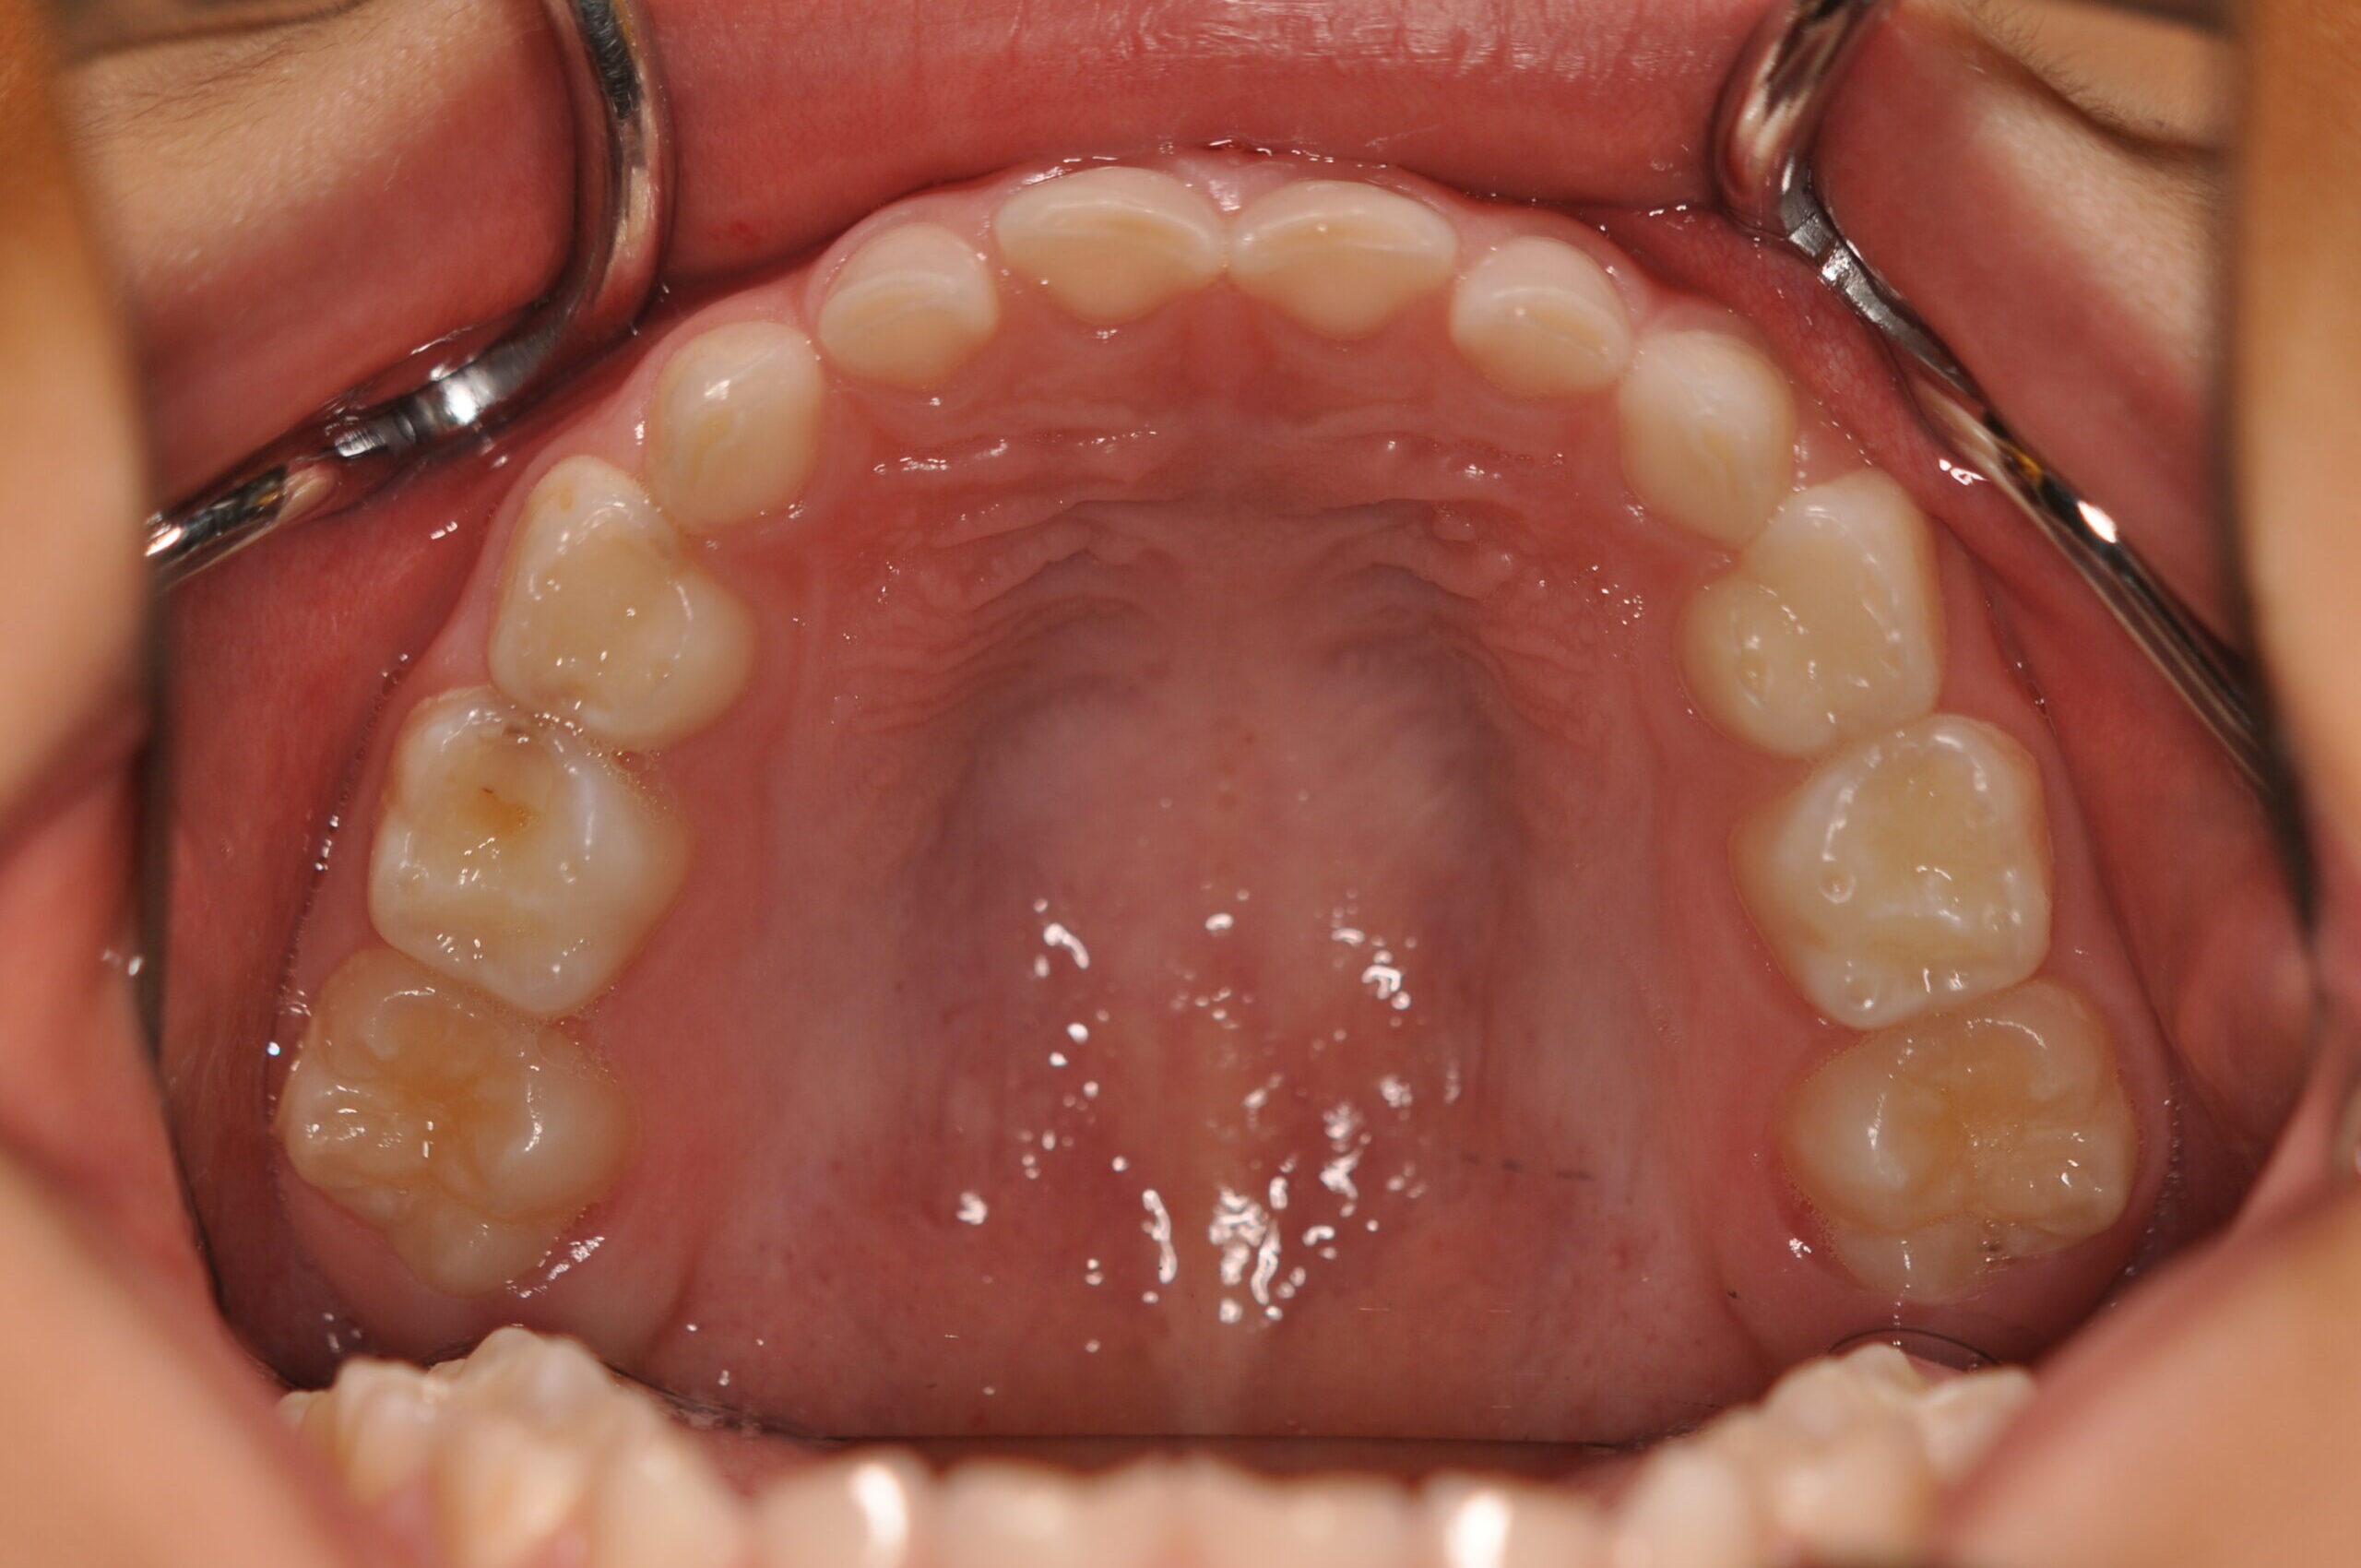

| 治療内容の詳細 | 初診時6歳の男性で、受け口を気にされ来院されました。 検査の結果、反対咬合を伴うアングルⅢ級不正咬合と診断しました。 治療としては、初期段階の治療として、機能的矯正装置で鼻呼吸の獲得と舌の位置や口唇の閉鎖といった筋機能習癖の改善を行い、上顎前方牽引装置を使用し上顎骨の前方方向への発育を誘導し、反対咬合の改善を行いました。 永久歯列に交換後、非抜歯の上、セルフライゲーションブラケット装置(デーモンシステム)で歯の配列と咬合関係の改善を行いました。 治療期間は、7年3ヶ月でした。 |